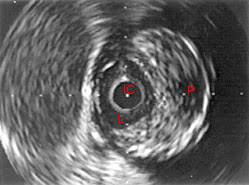

- la aplicación de ecografía intravascular durante cateterismos vasculares